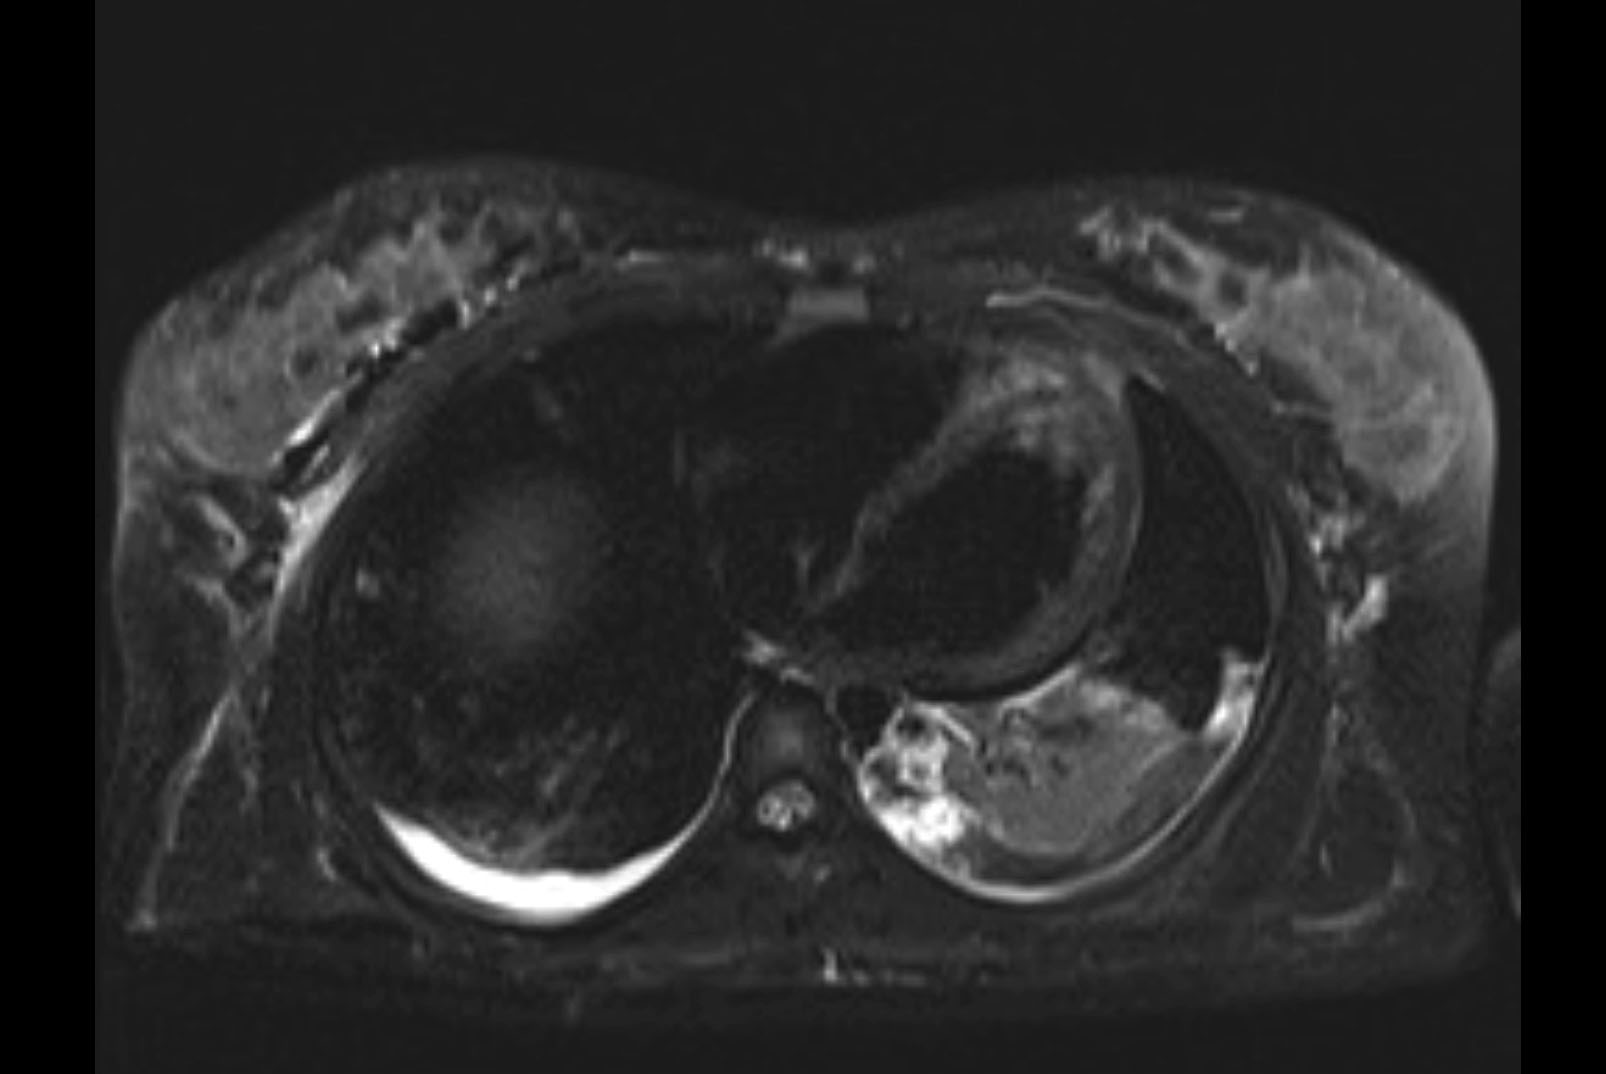

MRI T2

Imaging analysis

Based on initial findings, which issue(s) would you be most concerned about?